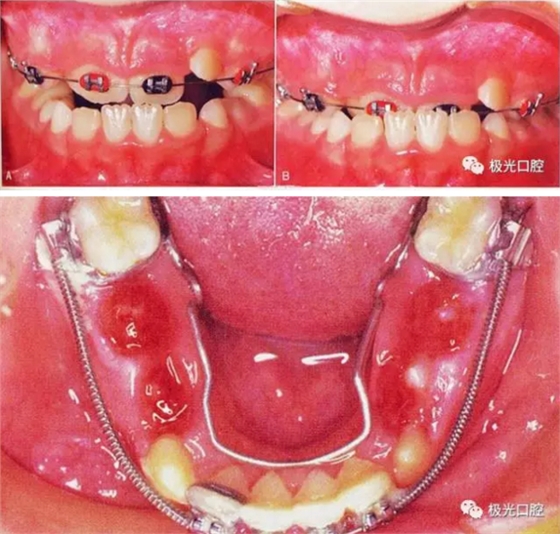

部分患兒在5-8歲左右,由于乳牙反咬合或者牙弓過窄等情況,經(jīng)過口腔狀況評估,醫(yī)生可能會建議使用預(yù)防矯治器或片段弓來解決。

簡單來說這款就是兒童常用的矯治器,主要用來預(yù)防。

三、擴(kuò)弓器

很多牙列不齊常伴隨牙弓過窄,所以擴(kuò)弓器是正畸醫(yī)生的好伙伴,它可以以多種形態(tài)和您見面。以下是幾種常見的擴(kuò)弓器,想想您的口腔內(nèi)將安放這些東西……